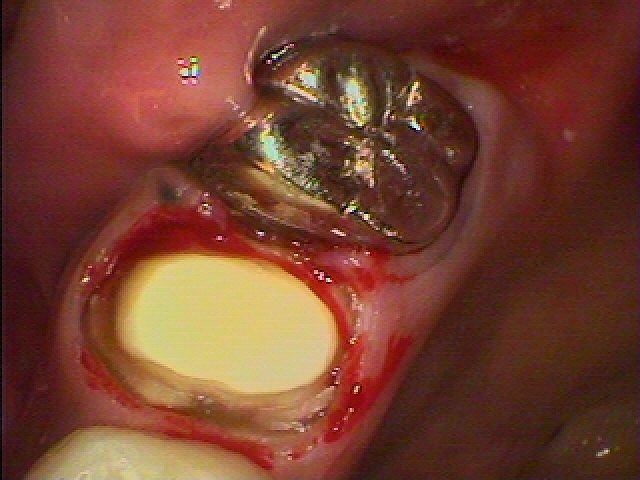

根充後ファイバーコアを築造後、支台歯形成を行っています

ディープシャンファーにて支台歯形成しています

1週ぐるりと支台歯形成してあります